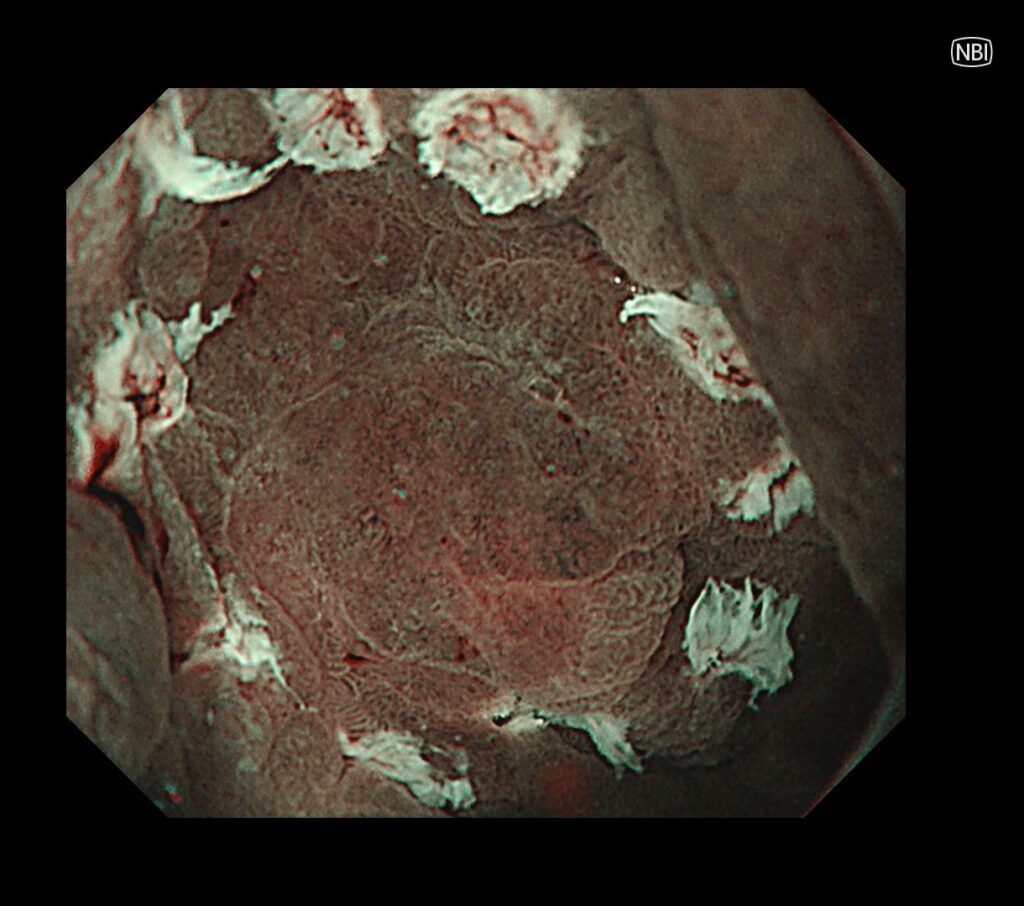

硬そうな瘢痕近傍に癌があることが、みてとれると思います。

瘢痕近傍は全く視野確保がとれないため、独自で作った糸付きクリップで、病変を牽引し、切除ラインを視認しやすくします。

約30分で胃がんの切除完了しております。